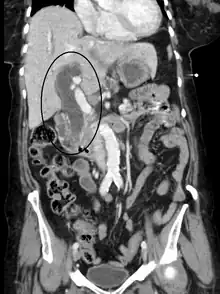

Biliary-tract dilation due to obstruction as seen on CT scan (frontal plane)

Biliary-tract dilation due to obstruction as seen on CT scan (axial plane)

Most people presenting with jaundice have various predictable patterns of liver panel abnormalities, though significant variation does exist. The typical liver panel includes blood levels of enzymes found primarily from the liver, such as the aminotransferases (ALT, AST), and alkaline phosphatase (ALP); bilirubin (which causes the jaundice); and protein levels, specifically, total protein and albumin. Other primary lab tests for liver function include gamma glutamyl transpeptidase (GGT) and prothrombin time (PT).[37] No single test can differentiate between various classifications of jaundice. A combination of liver function tests and other physical examination findings is essential to arrive at a diagnosis.[38]

Medical imaging such as ultrasound, CT scan, and HIDA scan are useful for detecting bile-duct blockage.[41]